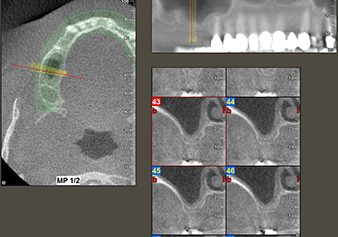

A 49-year-old female patient, a non-smoker and with nothing remarkable in her general medical history, was referred to our oral surgery practice for surgical extraction of tooth 16 and subsequent implantation. After the extraction, the patient experienced mild sinusitis trouble with the resultthat we initially waited six months before carrying out the measure. The residual bone height at the planned implant position measured 3-4 mm (Fig. 1 and 2).

The I2A instrument (diameter 2.0 mm) was then used to perforate the sinus floor intermittently and on the smallest scale possible. This special piezosurgical method ensures that the Schneiderian membrane is not damaged. When the Z25P was used, the membrane was already lifted slightly by the coolant supplied via the instrument tip (Fig. 3). The coolant quantity was just 50% in order to avoid high pressure in the implant bed.